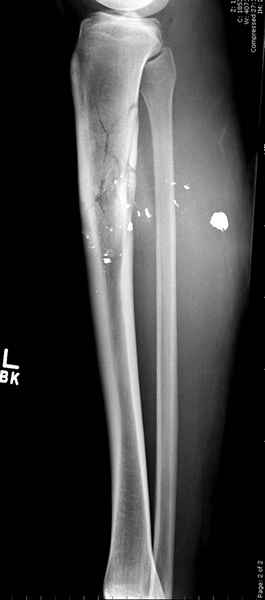

3 такие раны после удаления пули и остатков одежды можно закрыть первично